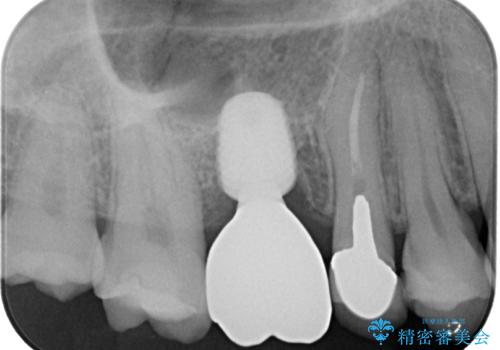

割れてしまった奥歯 1DAYインプラント治療

- 近医にて治療がなかなか進まないとのことで来院された患者様です。

詰めている材料を外したところ、目視で確認できるほど割れており、要抜歯との説明をし、インプラント治療を行うこととしました。

骨量が十分にあることが3次元CTより確認されたため、事前に仮歯を用意した上で、抜歯即時埋入インプラントによる補綴治療を行うこととしました。